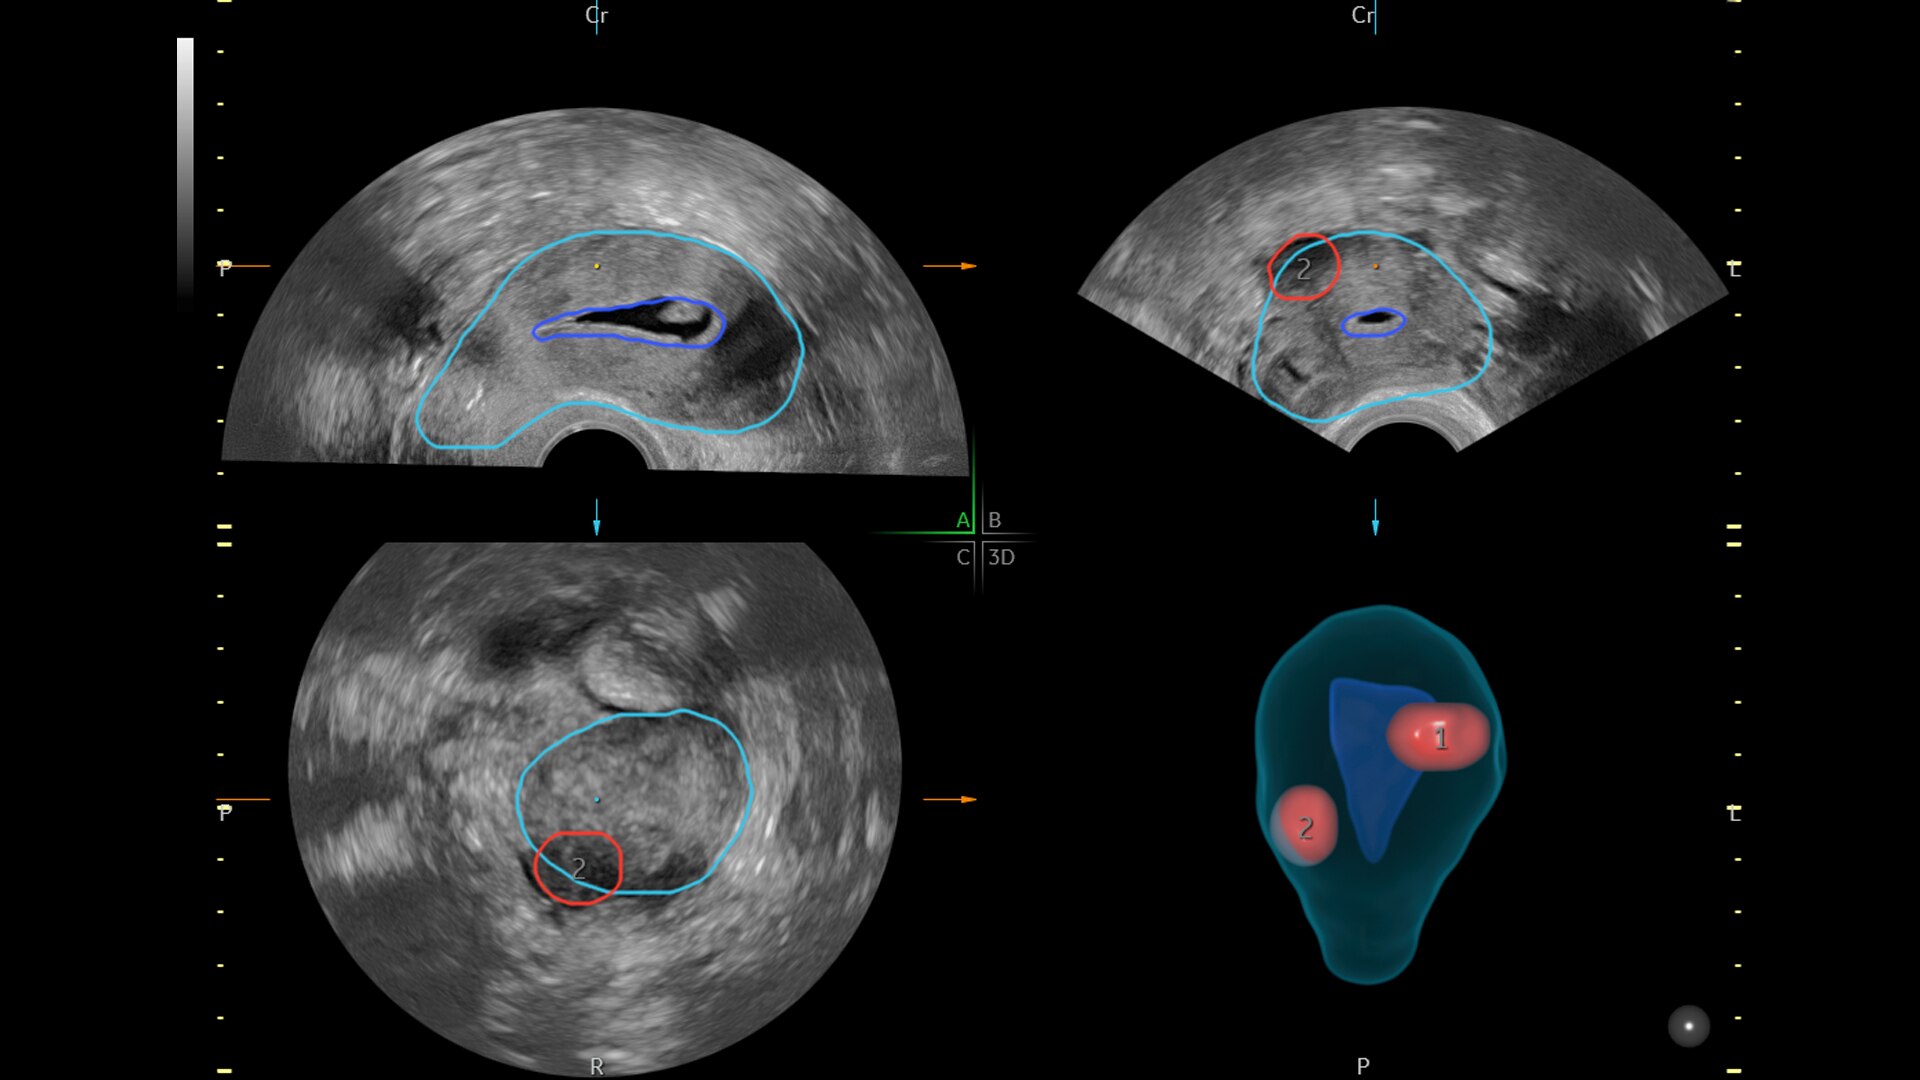

SonoGYN

Combines our Uterine Trace tool and Fibroid Mapping feature, an AI reporting tool that standardizes and streamlines fibroid documentation by mapping, measuring, and classifying fibroids in 3D.